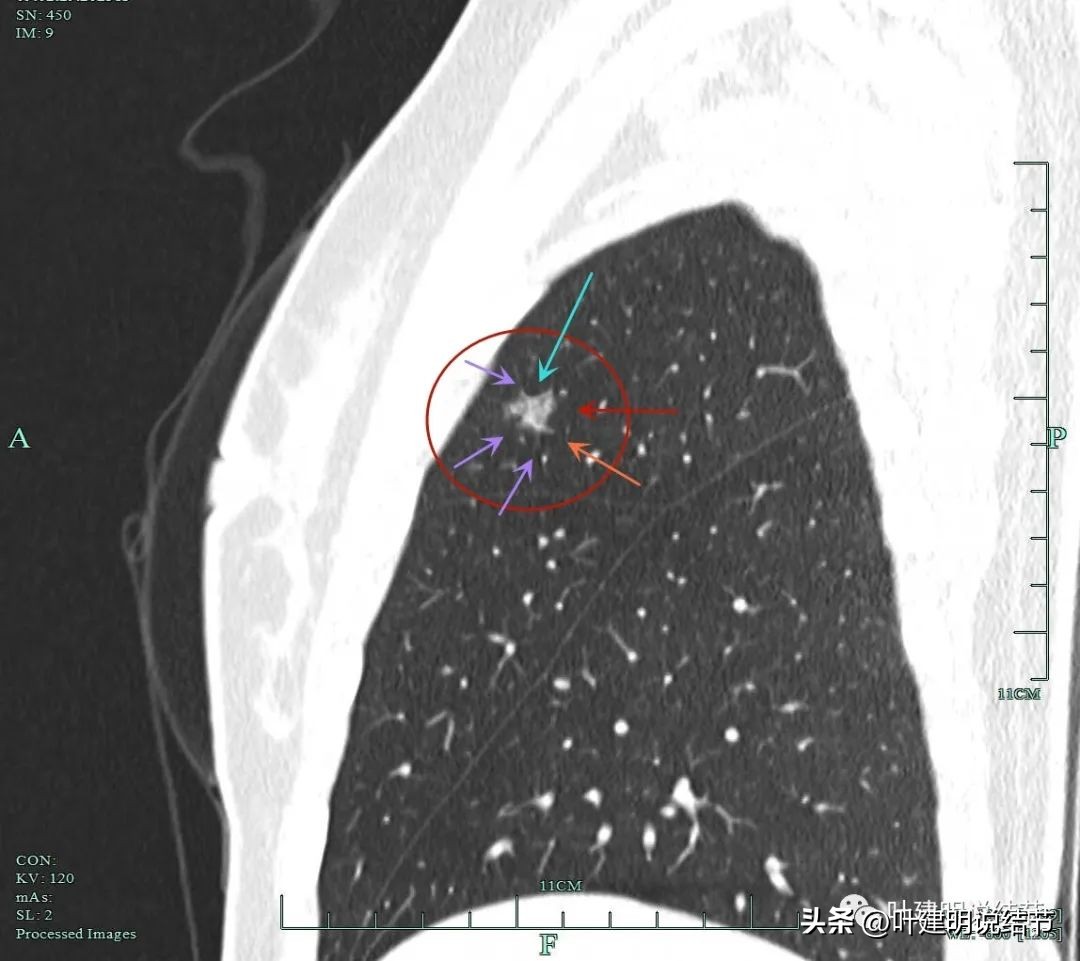

主病灶靶扫描重建影像:

蓝色箭头示月牙铲征;紫色箭头示毛刺或棘突征;桔色箭头示有血管进入并穿行与异常增粗;红色箭头示病灶轮廓与瘤肺边界清楚。